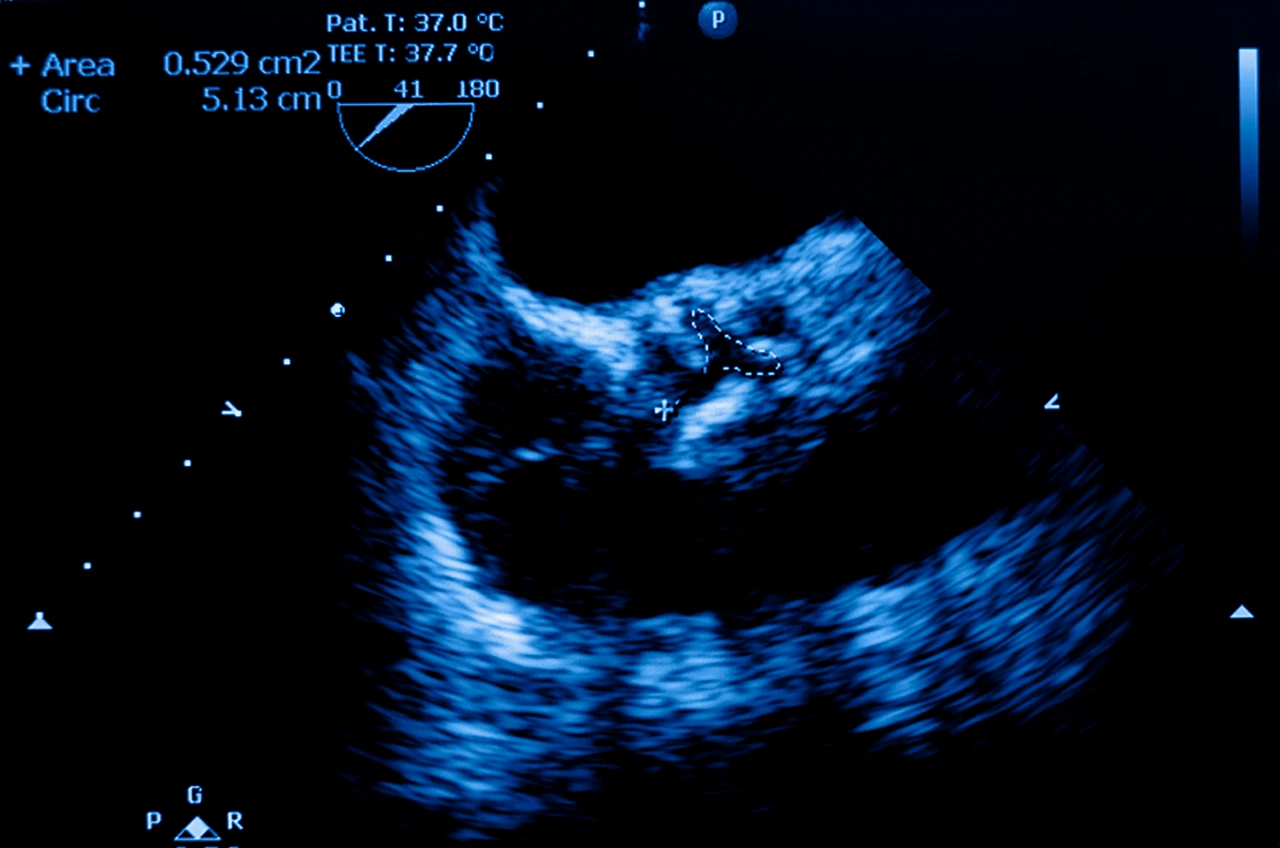

• Ecocardiograma: principal estudio para visualizar la válvula aórtica, medir el flujo sanguíneo y clasificar la estenosis.

Ecocardiograma donde se visualiza la presencia de estenosis aórtica severa en un paciente.

Estas herramientas permiten clasificar la enfermedad con base en la estenosis aórtica clasificación, que considera el grado de estrechamiento y la presión que debe ejercer el corazón para vencer la obstrucción.